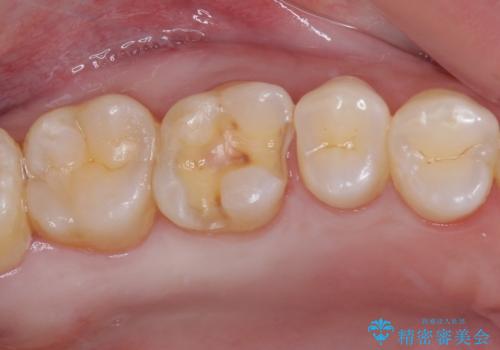

- 銀歯をセラミックにしたいとのことで来院された患者様です。

まず麻酔をして銀歯を外し、むし歯を除去し、形を整えて型取りします。

そして次の来院時、セラミックインレーを装着し、噛み合わせなどの調整を行います。

それを左右に分けて行いました。

インレーを装着するときは、唾液や血液による接着力の低下を避けるためにラバーダム防湿を行いました。